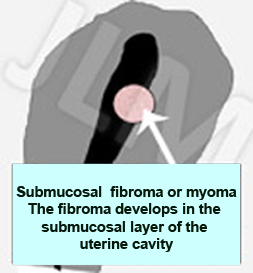

When fibromas occur within the uterine cavity they are termed submucosal fibromas. They can provoke heavy or prolonged bleeding (menorrhagia) sometimes with clots. They can also lead to infertility since the ball like growth can inhibit successful embryo implantation.

When fibromas occur within the uterine cavity they are termed submucosal fibromas. They can provoke heavy or prolonged bleeding (menorrhagia) sometimes with clots. They can also lead to infertility since the ball like growth can inhibit successful embryo implantation.